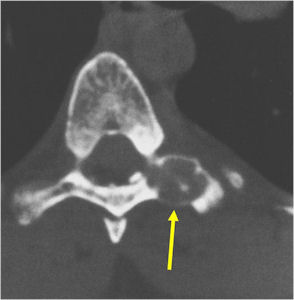

- Spine (40% of cases; usually posterior elements)

Plain X-rays:

- Geographic, circumscribed lesion usually around 5cm in size.

- There may be expansion of bone, cortical thinning and cortical breakthrough. A soft tissue mass may accompany this lesion but the soft tissue component is usually contained by the periosteum.

- The periosteum remains intact around the soft tissue component. Might need a CT scan to detect the subtle calcification (Egg Shell Rim of Calcification) associated with an intact periosteal reaction

- The lesion may be entirely radiolucent but usually shows some degree of mineralization. Mineralization may appear stippled like cartilage but do not see chondroid pathologically. Mineralization is sometimes better detected on a CT scan rather than an x-ray.

CT Scan:

- More useful for detecting mineralization and evaluating extent of bone destruction than plain X-ray